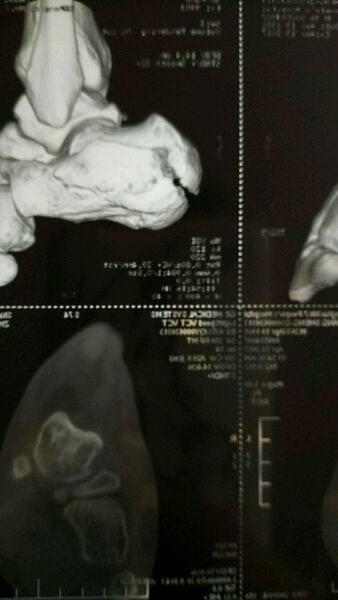

开贴记录下右粉

跟骨骨折吧

骨折十天了,在家消肿,今天来医院住院,还是有点肿,预计后天手术

没有,就是右根骨粉碎,位移

手术做好了,一板八钉,半麻,手术时常两小时

看来不算严重,从上掉落了的吧

是的,货车上跌落,1.3米高